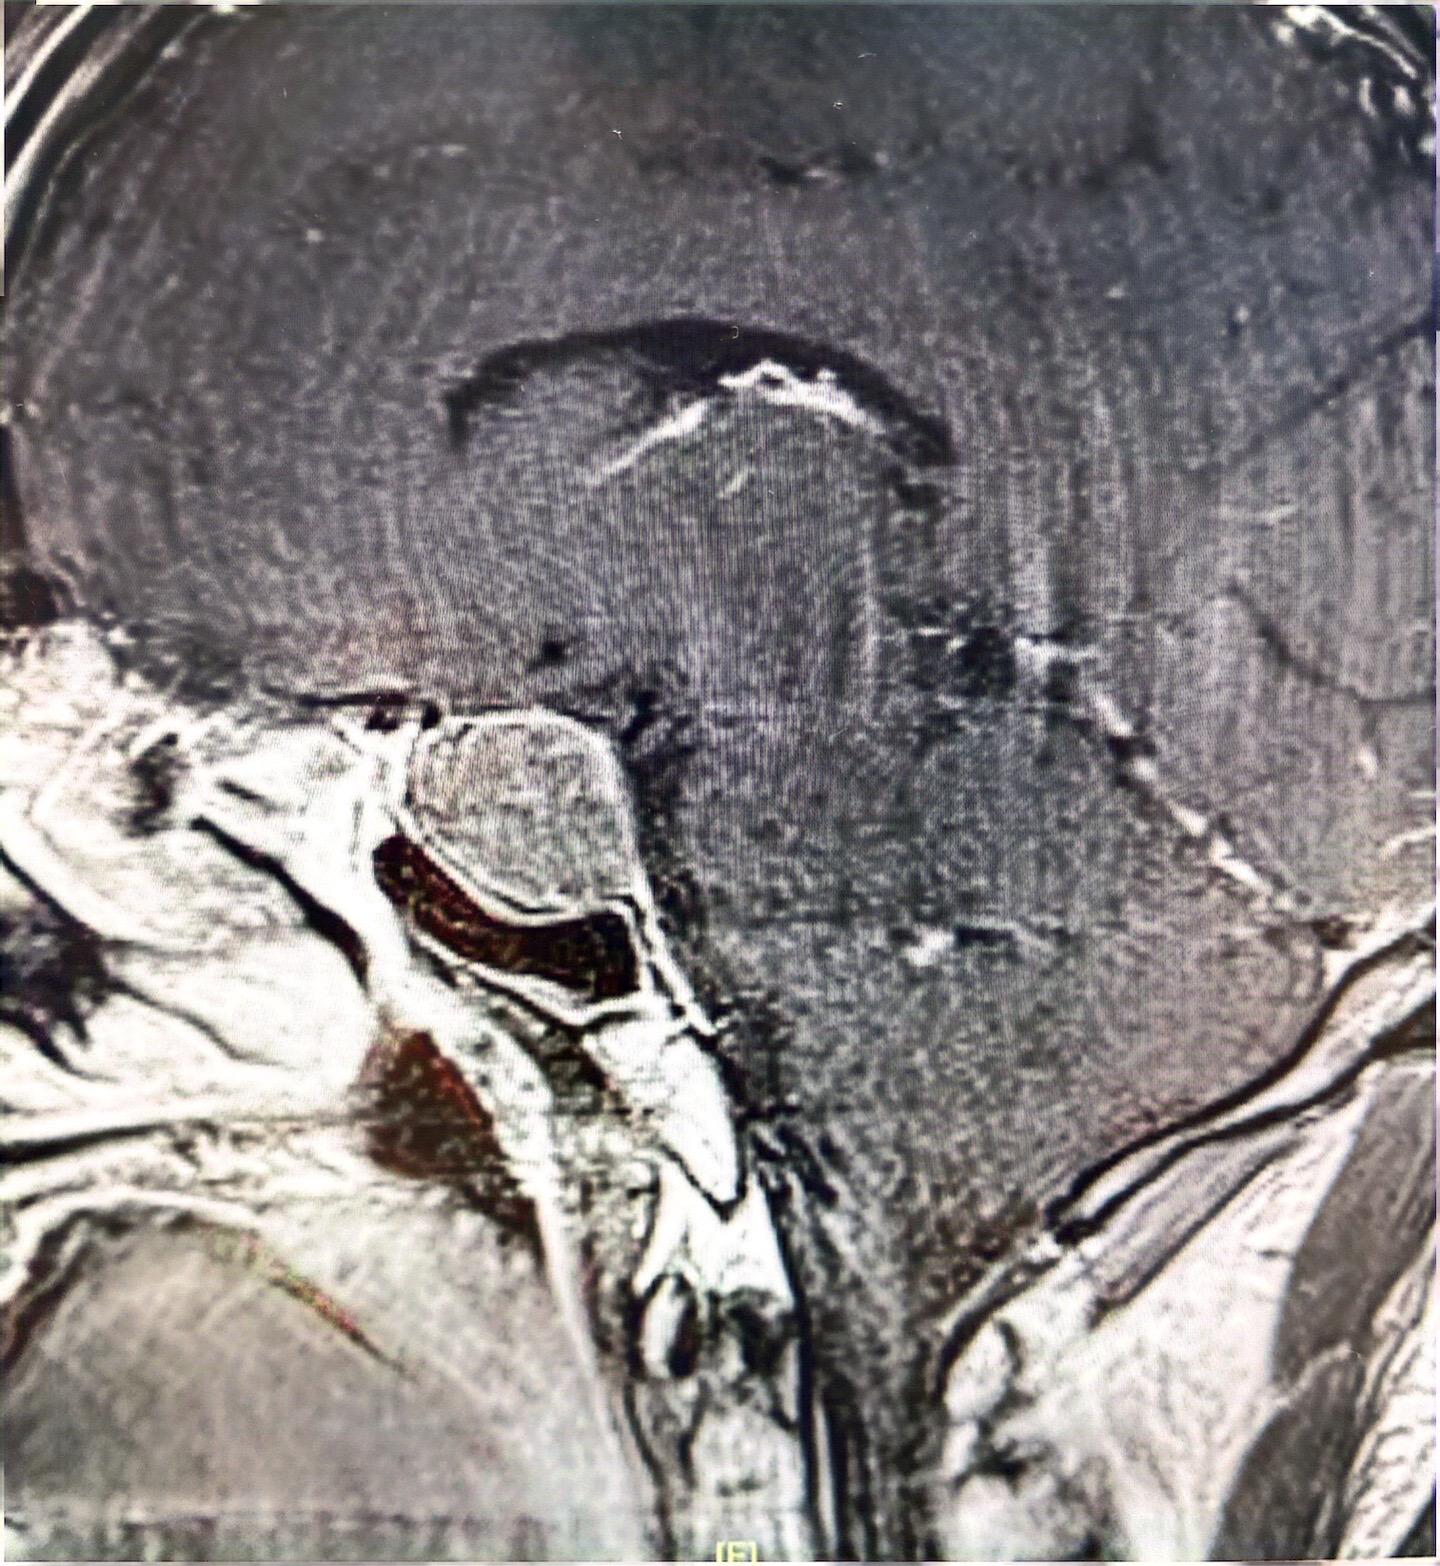

垂体瘤(生长激素型)分泌型垂体肿瘤难度还是较大,经鼻子手术,双镜联合,同时术中磁共振辅助,术后生长激素终于恢复正常!